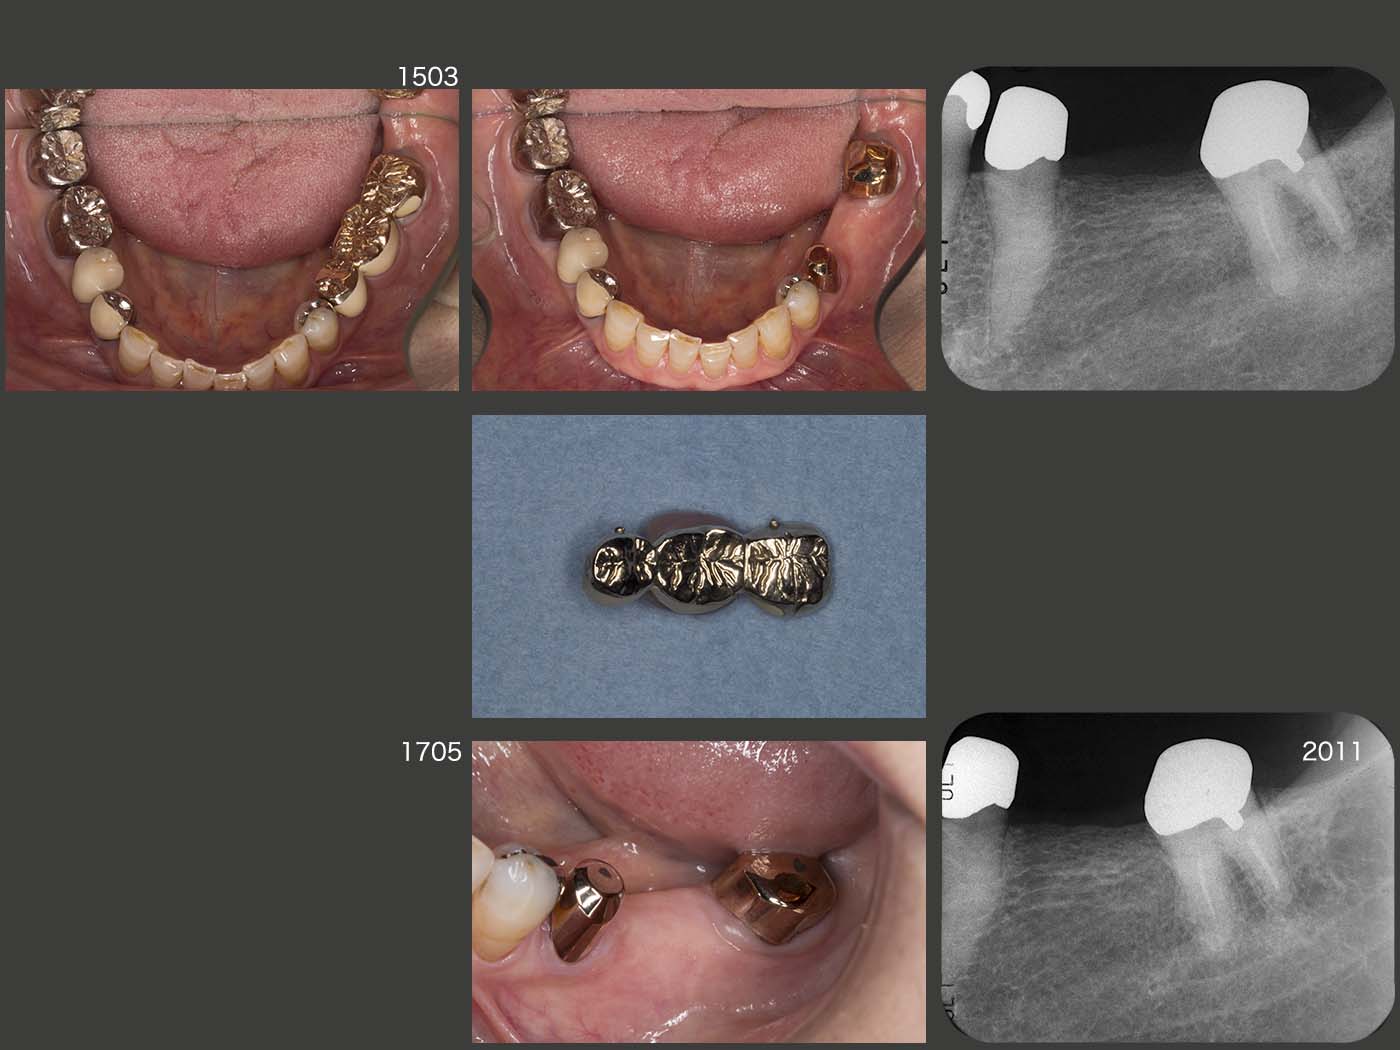

以上の準備が整ったところで,2016年6月に右上3および左上1を固定源として,右上1,2および左上3の再植を同時に行った.この際,歯肉縁上歯質が得られるところまで挺出し,ワイヤーに固定した.

デンタルX線写真は,術後2ヵ月半の状態であるが,右上2の動揺は収まらなかった.また左上3の遠心に7mmの歯周ポケットが残ったため,同部の歯肉切除を行った.

治療途中に骨折等で通院できず,治療期間は延びてしまったが,2017年12月に上下顎にコーヌス義歯を装着した.再植した右上2は動揺があるため側方力をかけないように根面板を装着するに留めた.左上3は若干の動揺があるため,少し丈の短い内冠を装着した.右上1は通常の長さの内冠を装着した.なお,3本の再植歯の歯周ポケットは3mm以下に落ち着いた.